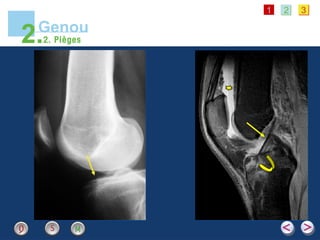

Fracture plateau tibial postérieur (LCP)

Témoin osseux indirect

d’une rupture du LCA

+/-

lésion ménisque interne

Fracture de Segond

• #18 - A gauche, cliché de profil de genou d’un jeune homme de 20 ans qui présente une douleur aiguë suite à un mouvement de torsion en flexion-rotation interne du genou, lors d’un match de football. - A droite, IRM en séquence T2, incidence sagittale du même patient - Chez ce jeune patient, cette IRM complémentaire a été réalisée à la demande du chirurgien orthopédiste. Cette IRM montre une lipo-hémarthrose [étoile jaune] et une parfaite intégrité du ligament croisé antérieur [flèche jaune]. Ce cliché en pondération T2 confirme le diagnostic de fracture avec présence d’une image linéaire en hyposignal donc noire [flèche courbe] silhouettée par l’oedème périphérique en hypersignal donc blanc. - Ce type de fracture du plateau tibial antérieur est relativement rare [flèche jaune]. Il survient chez le jeune adolescent, dont le ligament croisé antérieur est plus solide que son attache osseuse. Lors d’un mécanisme mettant en tension le ligament croisé antérieur, celui-ci demeure continu alors que survient une fracture-arrachement de son insertion tibiale.

• #19 Cliché de face et de profil chez un patient présentant une suspicion clinique de rupture du ligament croisé postérieur. De face, on devine une fracture de l’épine tibiale externe se prolongeant en sous-tubérositaire [flèche jaune]. La fracture du plateau tibial postérieur est bien visible de profil avec un décalage cortical net [flèche jaune]. Ce type de fracture est le pendant de la fracture précédente correspondant à un arrachement de l’insertion du ligament croisé postérieur.

• #20 Cliché réalisé après une entorse du genou. Avulsion osseuse de petite taille du bord latéral du plateau tibial, située juste en dessous du rebord articulaire [flèche jaune]. La fracture de Segond correspond à une avulsion osseuse située en-dessus et en dehors du tubercule de Gerdy. - Elle est secondaire à un mouvement en varus et rotation interne qui produit une avulsion de l’insertion du 1/3 moyen de la capsule articulaire latérale. - Cette fracture est importante à diagnostiquer, malgré un aspect radiologique minime, car elle est quasiment toujours associée à des lésions du ménisque interne et à une rupture du LCA, ce qui en fait toute sa gravité. [Apparition du titre]